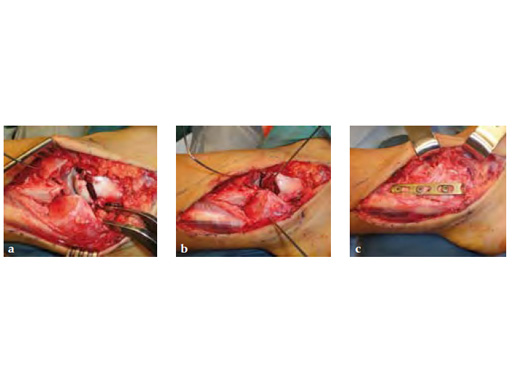

Fig 2ac Intraoperative images.

A 20-year-old construction worker fell from a 3 m height. He sustained a typical posterolateral impression and flake fracture of the talar dome.